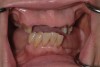

Fig 17. Pre-treatment smile of patient with terminal dentition.

Figure 17

Fig 18. The patient’s intraoral condition.

Figure 18

Dental rehabilitation with the All-on-4 treatment concept is often a life-changing event for edentulous and terminal dentition patients that results in unprecedented quality of life improvements (Figure 17 through Figure 20).